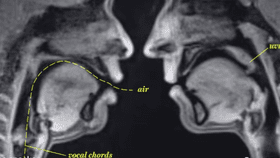

Have you ever wondered what sex would look like if you were able to see INSIDE the bodies of the participants? No? Just me?

The rest of this article is behind a paywall. Please sign in or subscribe to access the full content.Well, even if you haven't wondered, you can now find out.